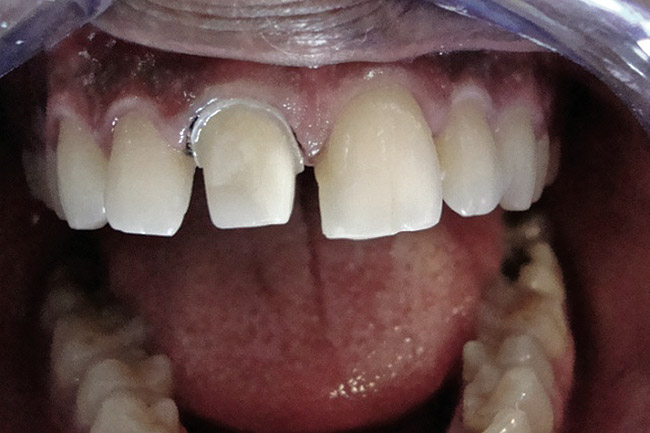

Figure 4  Final composite restorations with respect to upper right incisors.

Figure 4